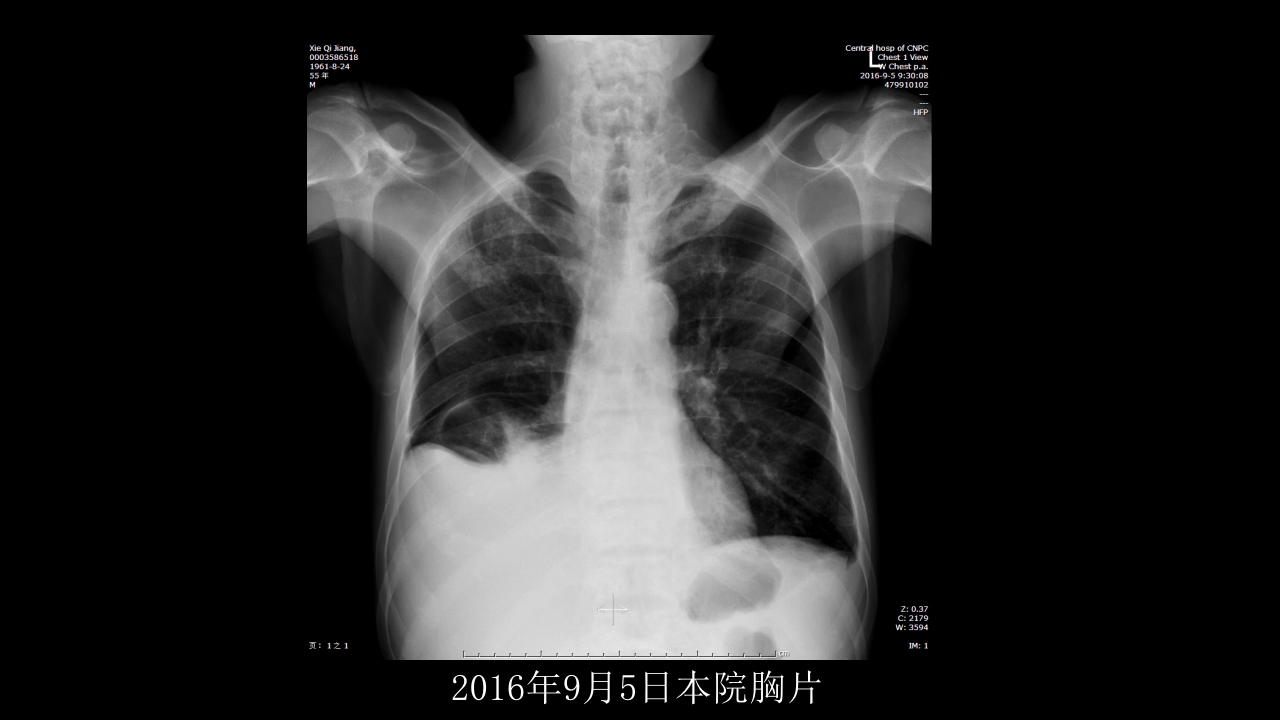

没有见过的弥漫性的骨质破坏